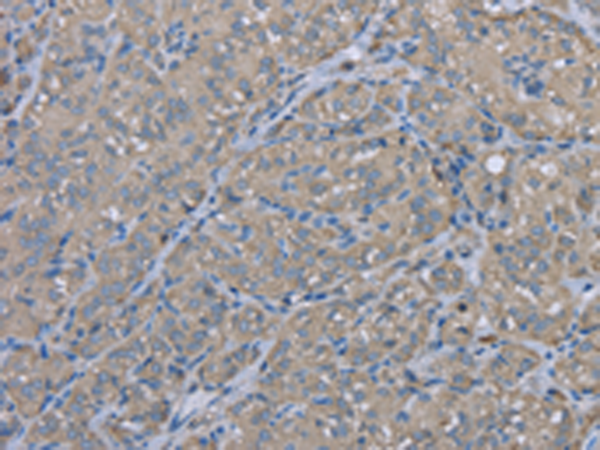

分类: 科研抗体货号: P08310别名: MTVR1应用: WB,IHC反应种属: Human, Mouse